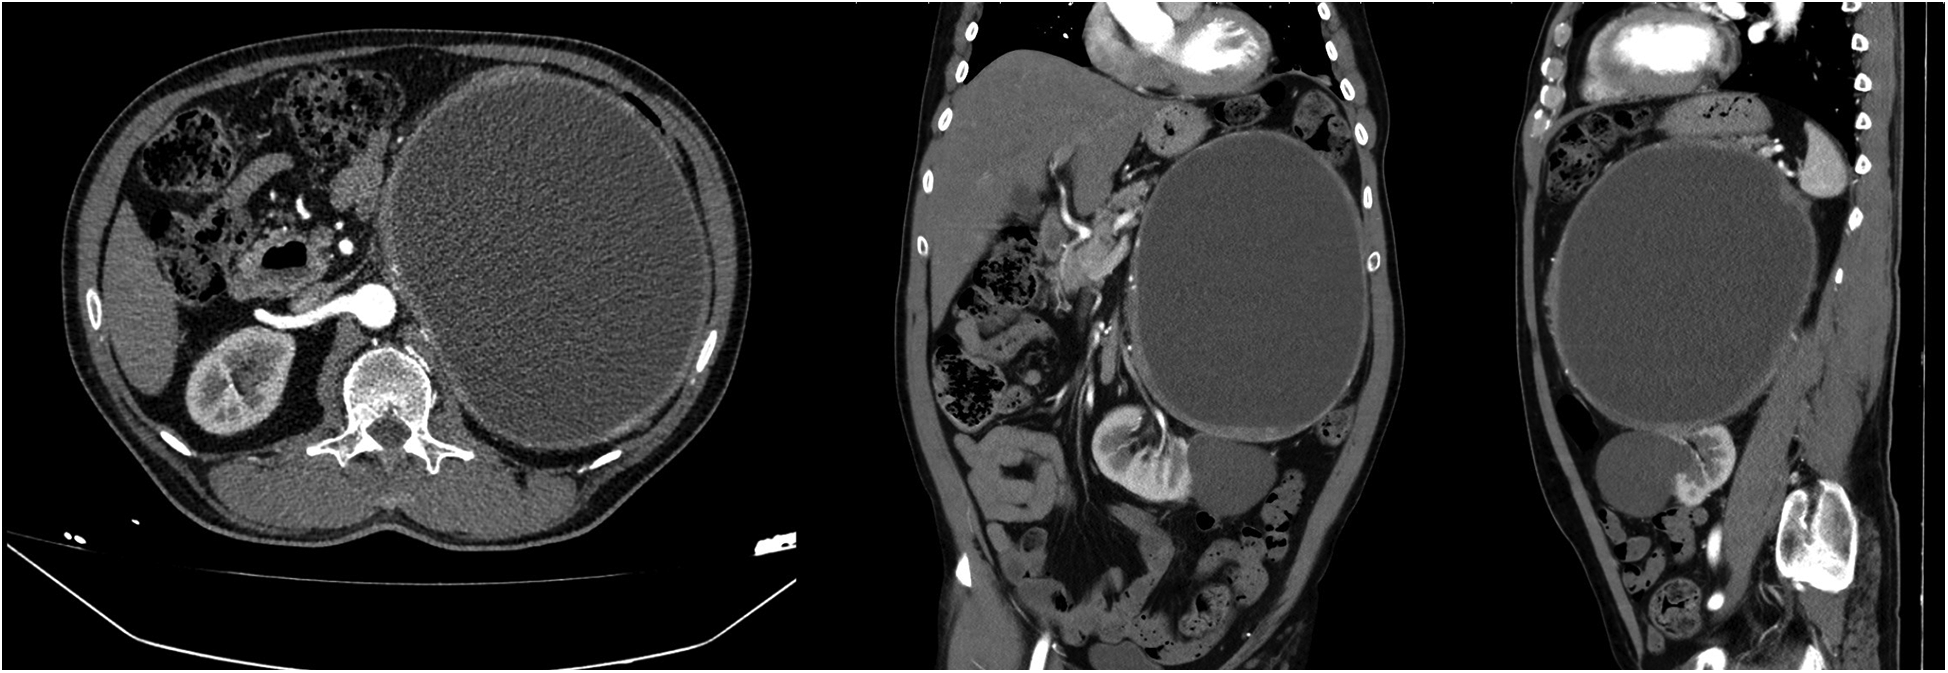

Contrast-enhanced computed tomography (CT) revealed a huge cystic mass measuring 22 × 17 cm, originating from the left adrenal gland. The mass has regular borders and a contrast enhancement of the wall. Because of this huge mass, the left kidney appeared malrotated, was displaced inferomedially and was observed in the para-aortic area (Figure 1). A large parapelvic cyst measuring 6 × 5.5 cm was also observed in the left kidney (Figure 1). The patient underwent 18 F-fluorodeoxyglucose positron emission tomography (PET)-CT imaging for diagnosis confirmation and metastasis determination and no metastatic involvement was detected.

Figure 1

Computed tomography images of a giant left adrenal cystic mass and a left renal large parapelvic cyst.